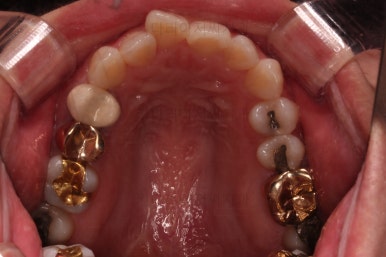

이번에 부산부분치아교정 환자분이 선택하신 장치는 엠파워 클리어라고 하는 자가결찰 세라믹인데요.

흔히들 아시는 클리피씨가 이러한 종류의 장치에요.

아랫니는 일반 브라켓 보다 매우 작은 장치가 들어갔는데요.

미니튜브 장치에요.

일반적으로 MTA 장치라고 많이 알려져 있는데요. MTA라는 상품명과는 다른 장치이긴한데 왜 이 장치를 사용했을까요?

보기도 덜 보이는 장점이 있지만 이번 환자분의 경우에는 아랫니가 약간 솟구쳐 오르면서 장치를 부착하게 되면 씹혀서 매우 불편감이 예상되었었어요.

그래서 초기 정렬단계에서는 미니튜브를 이용해 주고, 추후에 좀 더 정교한 조절이 필요한 상황에서는 브라켓장치(엠파워 클리어)로 재부착하기로 했어요.

그리고 아랫니 송고니 옆 잇몸에 보시면 미니스크류가 식립이 되어있는데요.

이는 솟구친 아래 앞니의 높이를 조절하기 위해 사용이 됩니다.

이부분이 해결이 되어야 좀 더 완성도 높은 부분교정이 가능해요.